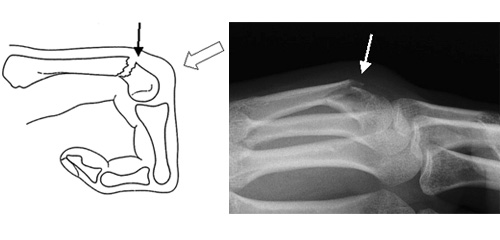

ボクサー骨折 2カ月放置 2025年12月10日 最終更新日時 : 2025年12月10日 masui 格闘家の方です。ボクサー骨折は多くがパンチ動作で発生するためボクサー骨折とも呼ばれます。環指や小指の中手骨が多いです。こぶしを含めた手の甲の先端部分が腫れ、痛みのために指を動かしにくくなり、骨折した指のこぶしが凹んで見えます。2か月前に骨折したのは分かっていたが放置。痛みが残ってしまったので来院。患部に電気針を希望で施術いたしました、腫れは引きましたが、継続的な治療が必要です。怪我は放置せず早期治療しましょう \ 最新情報をチェック / Page Views 201 FacebookXBlueskyHatenaCopy